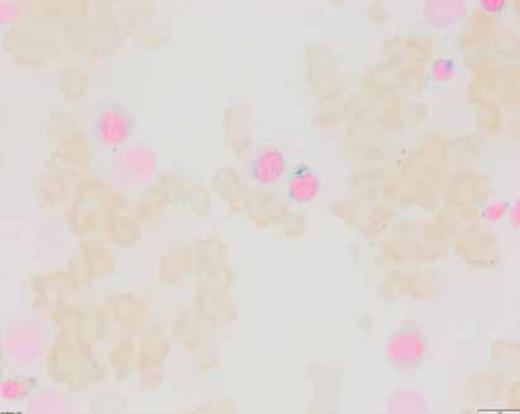

Peripheral blood smear. The figure shows marked anemia and neutropenia with adequate platelets.